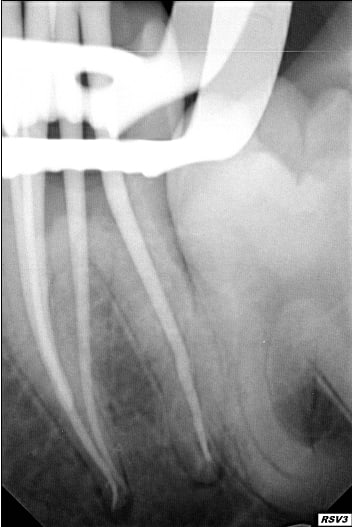

Moins impressionnant que les cas d'esthétique des pages précédentes mais je suis content de mon endo 4 canaux ;)

O 02e7d4f0bd462f70 0 cmqift - Eugenol

O 1958718cc4fe96b5 0 bjixou - Eugenol

As-tu une radio de cette dent reconstruite ?

J'espère que tu as prévu une élongation coronaire en distal.

ça va, il y a de l'os.

Edit: c'est peut-être aussi un artéfact avec le métal du clamp, bien que sur la 1ere radio on semble bien être en sous-crestal.

neb et malaire : j'ai eu la joie de faire un amalgame trois faces, le patient ayant l'AME et n'ayant pas envie de sortir 750 euros pour un inlaycore-ccm

oui c'est énervant

mais j'étais prévenu avant de faire l'endo

Ceci dit belle endo.